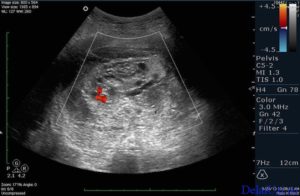

Данный вид исследования в кругу врачей считается более точным. Обычно именно он назначается для изучения состояния органов малого таза. Возможным считается также его применение при беременности на ранних сроках.

По результатам вагинального УЗИ можно выяснить стадию развития плода, рассмотреть самые незначительные аномалии и выяснить причину повышенного тонуса живота. Насколько необходимо проведение этой процедуры на маленьком сроке, решает непосредственно врач. Обычно это связано с какими-то патологиями, заболеваниями матери или проявлении негативных симптомов (кровотечение, боли внизу живота).

Трансвагинальный датчик используют в первом триместре только в случае сомнительных результатов обычного УЗИ. Такой вариант помогает лучше просматривать матку и придатки из-за близости к этим органам. При процедуре во влагалище вводят тонкий прибор, на который надевают презерватив.

Киста яичника, миома, эндометриоз, аденомиоз, раковая опухоль — все эти патологии характеризуются мажущими кровянистыми выделениями, но с действием трансвагинального датчика УЗИ это никак не связано.